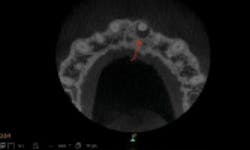

Figure 3: Apical lesion on tooth No. 9 looks suspicious on 2-D radiograph, but could not be diagnosed definitively

I examined a patient who had experienced trauma to his two front teeth approximately five years prior and was now experiencing occasional pain. From an x-ray, the problem could not be diagnosed as definitive (figure 3). However, as soon as I took the 3-D image, I could see an abscess, which required a root canal (figures 4–8).